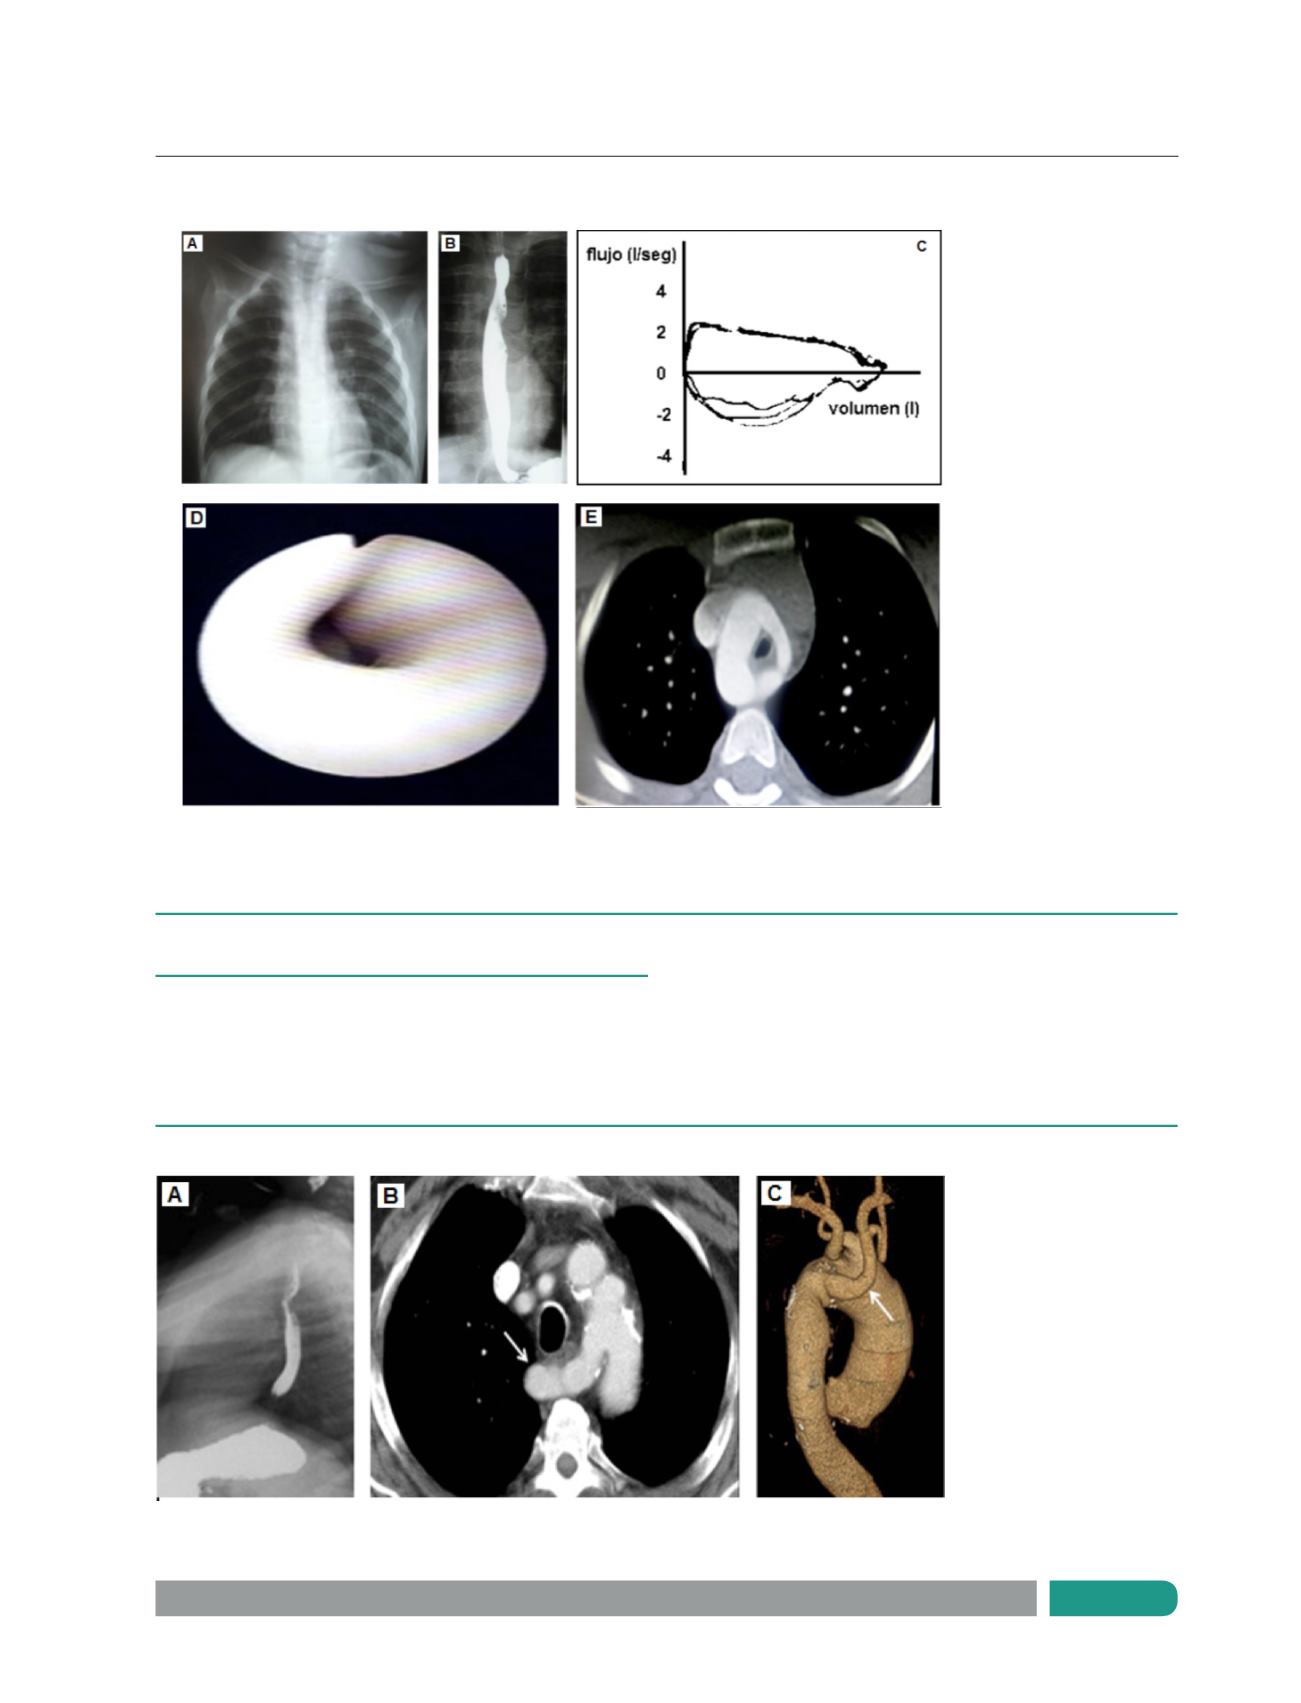

Figura 1.

Niña de 9 años de edad, doble arco aórtico.

Figura 2.

Niño de 7 años, arteria subclavia derecha aberrante.

A:

Radiografía de tórax: desviación de la tráquea hacia izquierda.

B.

Esofagograma: muesca esofágica.

C.

Curva flujo/volumen: obstrucción fija de vía aérea.

D.

Fibrobroncoscopía: compresión traqueal extrínseca pulsátil.

E.

TAC tórax: doble arco aórtico.

Esofagograma compresión esofágica.

AngioTAC Tórax: compresión esofágica.

TAC tórax con reconstrucción:

arteria subclavia derecha aberrante.